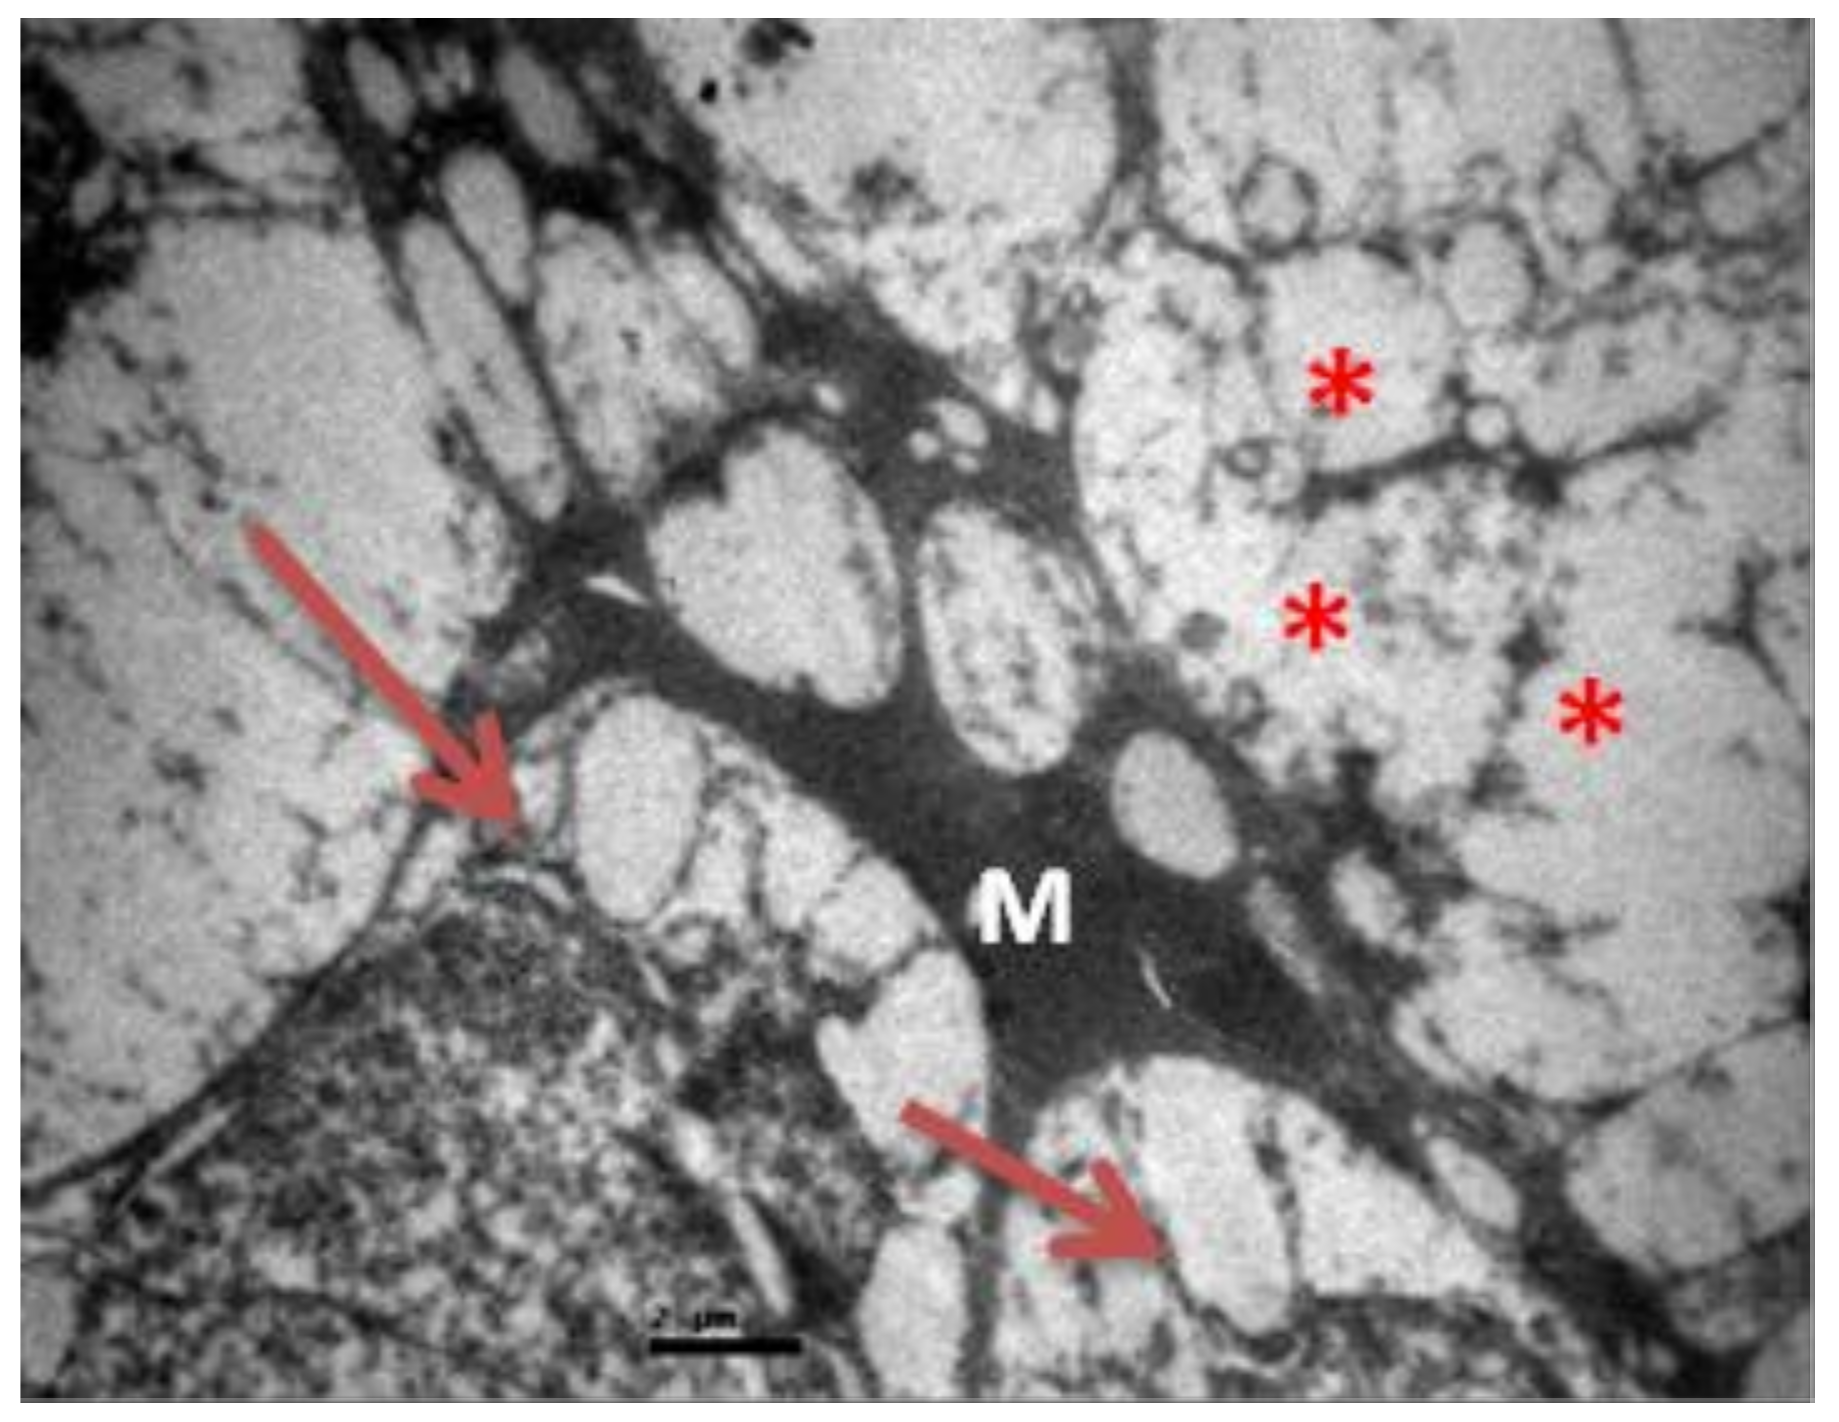

2.1. Group C

2.2. Group V

2.3. Group M